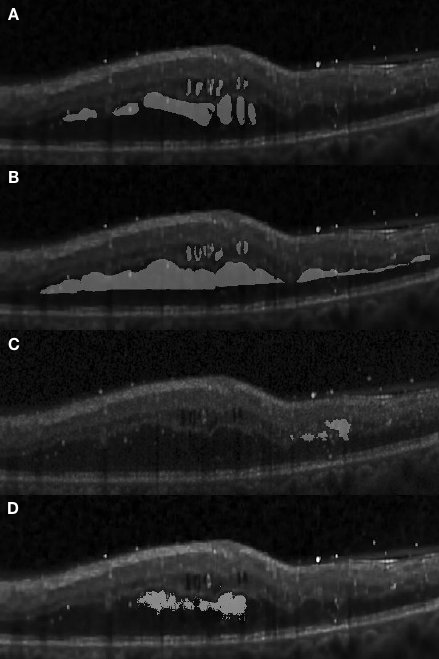

Apart from the segmentation of large areas, there are still some cases where our approach failed to segment the target region accurately. One such event occurred when small target regions were not segmented out, as shown in Fig. 4.1 (D). In this case, the small regions were affected by speckle noise and smoothing effects caused by the pre-processing resulting in the small regions being undetectable by the framework, due to their small initial size leading to them being smoothed out after several pooling layers. In another case, some target regions were only partially segmented, as shown in Fig. 4.4.

Figure 4.5 depicts the comparison of our method with the one reported in Chiu et al. [19] for three segmentation attempts carried out complex retinopathy conditions. It is found that Chiu’s method performs a slight over-segmentation near the bottom area. The segmentation results carried out with our method are closer to those which have been manually segmented. In Fig. 4.6, three images are shown which depict segmentation results on concrete and non-obvious fluid edema. The over-segmentation noted earlier can also be observed , as well as a false segmentation happening in the region on the left-hand side. Again, the results obtained with our method have a better agreement with those obtained via manual segmentation. Furthermore, our results are more adherent to target based on image content. This is also found in Fig. 4.7 where additional results are presented from the segmentation of an example of fluid edema. Quantitatively, we compared the Dice overlap coefficient and -value of Wilcoxon matched-pairs test for the DME region. Dice coefficients were calculated for all 10 patients and the process was repeated as per[19]. Specifically, the Dice coefficient was calculated based on all test images and the Wilcoxon matched-pairs test was calculated based on the mean Dice coefficient across all patients for our automated method and for the corresponding results from two graders. It was found that the Dice coefficient of our approach is standing for mean and standard deviation which outperforms reported in [19] (the higher, the better). Both methods are comparable with the Dice coefficient between manual graders ( ). The -value for our approach is , which is also better than reported in Chiu et al. [19] (where a coefficient value of indicates perfect agreement).